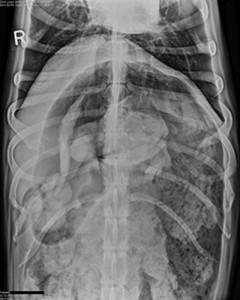

Radiografía del estómago del animal

A continuación, puedes ver la imagen de la radiografía del estómago del animal con todos los calcetines en su interior. Está claro que comer calcetines no es nada saludable en el menú de nadie. Pero lo más importante es que este entrañable animal se ha recuperado completamente.

"Los rayos X descubrieron una gran cantidad de material extraño dentro del estómago del perro, y se decidió operarlo para extraer todo el material” explica uno de los veterinarios. Sin embargo, "para gran sorpresa de todos, el material extraño resultó ser 43 calcetines. El perro se recuperó perfectamente y fue dado de alta al día siguiente".